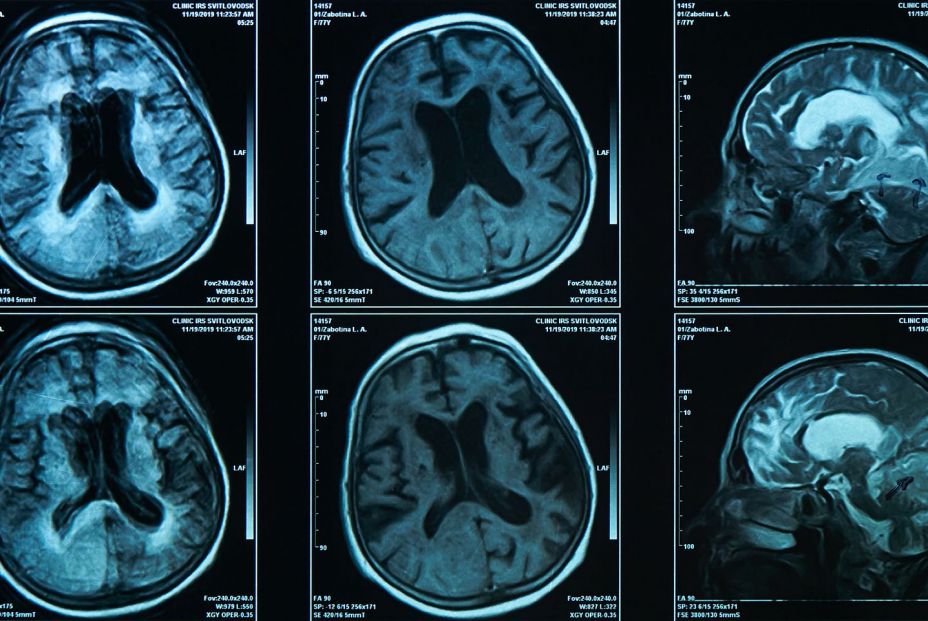

Un nuevo estudio detalla cómo los sistemas inmunitario y nervioso central implementan este comportamiento de enfermedad. En la investigación publicada en Cell, los científicos del Instituto Picower para el Aprendizaje y la Memoria del MIT y sus colaboradores utilizaron múltiples métodos para demostrar causalmente que cuando la citocina interleucina-1 beta (IL-1B) del sistema inmunológico llega al receptor 1 de IL-1 (IL-1R1) en las neuronas de una región del cerebro llamada núcleo del rafe dorsal, eso activa conexiones con el tabique lateral intermedio para detener el comportamiento social.

La IL-1B afecta a las células al unirse al IL-1R1, por lo que el equipo procedió a explorar el cerebro para determinar dónde se expresa este receptor. Identificaron varias regiones y examinaron neuronas individuales en cada una. El núcleo dorsal del rafe (DRN) destacó entre las regiones, tanto por su capacidad para modular el comportamiento social como por su ubicación junto al acueducto cerebral, lo que le otorgaría una alta exposición a las citocinas entrantes en el líquido cefalorraquídeo.

Los experimentos identificaron poblaciones de neuronas del DRN que expresan el IL-1R1, incluyendo muchas implicadas en la producción de serotonina, un neuromodulador crucial.